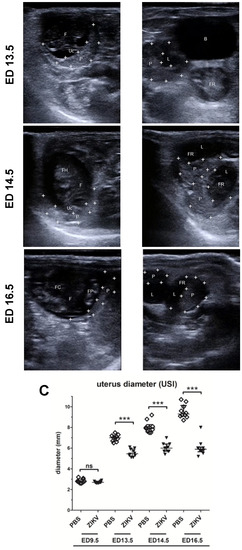

Figure 1.

Embryonic day (ED) 4.5: (A) + (B) A two-dimensional echocardiography image of the uterus showing the implantation site (uterus horn 1 (“U1”) and uterus horn 2 (“U2”) framed by white crosses) next to the bladder (“B”, shown in black) on ED 4.5.; ED 9.5: (A) + (B) Echogenic foci of the uterus horns are prominent on ED 9.5.; ED 13.5: (A) the placenta and the developing fetuses are visible (“P”, framed by white crosses, “F”) and the umbilical cord (“Uc”), (B) the placenta is visible in the uterus lumen (“P”, framed by white crosses, “L”, shown in black) and indistinguishable fetal structures (“FR”); ED 14.5: (A) growing fetus (“F”), with distinct structures such as the fetal head (“FH”), the umbilical cord (“Uc”) and the placenta (“P”, framed with white crosses) on ED 14.5, (B) the uterus lumen is either filled with fetal residues including the placentas (“FR”, “P”, framed with white crosses) or empty on ED 14.5; ED 16.5: (A) highly developed fetus with distinguishable fetal thorax, the fetal heart and paws (“F”, “FC”, “FP”) and the placenta (“P”, framed with white crosses) on ED 16.5, (B) Uterus lumen (“L”, shown in black) including placentas with unclear fetal residuals on ED 16.5; (C) Analysis of uterus diameter using USI at different timepoints during pregnancy (n = 8- 10dams per group, graph represents 2–3 independent measurements per uterus). Differences between individual groups were analyzed by Mann–Whitney test. Error bars indicate the interquartile range (IQR) from the median. Asterisks represent statistically significant differences between two groups: ns = non-significant, *** p = 0.0002; (D) Tabular summary of the ultrasound based findings as identified in (A,B) in the mock-infected mice (n = 20 fetuses, 4 examined fetuses/uterus ampoules per mouse and timepoint); (E) Tabular summary of the ultrasound based findings as identified in (A,B) in the Zika virus (ZIKV)-infected mice (n = 20 fetuses, 4 examined fetuses/uterus ampoules per mouse and timepoint).

To confirm pregnancy after positive plug-check, mice were examined on estimated ED 4.5 by ultrasound imaging (USI). Here sectional views (Figure 1, A+B, ED 4.5) showed substantial proliferation of both uterus horns (“U”) as seen in increased diameter relative to the bladder (“B”, shown in black). This increase is accompanied by proliferation of the mucosa as seen by higher echogenicity (image brightness in USI) on the sectional plane of the uterus. These observations confirmed the successful implantation process and mice that met these anatomical criteria as visualized by USI were considered positive pregnant and were included in this study.

These mice were analyzed by USI every day and representative images are shown in Figure 1 for EDs 4.5, 9.5, 13.5, 14.5, and 16.5. On ED 7.5 pregnant mice were either infected with ZIKV or with PBS as mock control. Two days after the challenge infection (ED 9.5) we observed continued growth of ampoules in both uterus horns, as seen by an average diameter of 2.8 mm for the PBS mock-infected mice (Figure 1 A, ED 9.5, “U1/2”, “B”, the bladder in black, Figure 1C) and an average in diameter of 2.6 mm in the ZIKV-infected mice (Figure 1B, ED 9.5, “U”, transverse sections in relative position to the bladder “B”, in black, Figure 1C). Of note, compared to the earlier embryonic stages as analyzed before, we succeeded in the imaging of two different sections through the uterus horn ampoules indicating an ongoing growth activity of physiological pregnancy for both experimental groups. These results indicate no obvious differences between PBS mock-infected mice and ZIKV-infected mice. On ED 13.5 USI identified a significant increase in the size of the uterus with a diameter of 7 mm in the mock-infected control group (Figure 1A, ED 13.5, Figure 1C). Of note bladder was not included in the picture using comparable insonation-angle (kept < 20°) supporting this observation. In addition, we were able to visualize highly echogenic structures (in USI brighter shades of grey) within the less echogenic (in USI darker shades of grey) liquid filled lumens of the uterus indicating a developing fetus (“F” in Figure 1A, ED 13.5).

A slightly brighter echogenic structure associated with the fetus suggested the starting formation of the first vessel structures. Under the tentative fetal structure another highly echogenic structure was visible that was identified as placental tissue (“P”, framed by white crosses). In ZIKV-infected animals we observed different uterus sections with a mean diameter of 5.5 mm indicating reduced fetal and placental development compared to the mock-infected control mice on ED 13.5 (Figure 1B, ED 13.5, Figure 1C). In addition, hypoechogenic structures within the uterus lumen demonstrated the presence of free liquids. Free liquids, identified as highly echogenic structures were also clearly detectable within the uterus lumen representing embryonic residues. Of note, bladder (“B”, black) still appeared in the USI while using the specific USI insonation-angle as established before. Another prevalent echogenic crescent-formed structure was visible on ED 13.5 in the ZIKV-infected mice showing the developing placental tissues (framed by white crosses).

On ED 14.5 USI in the PBS mock-infected group revealed the development of the ampoules with an average of 8 mm in diameter, corroborating the physiologic course of pregnancy (Figure 1C). This observation was further confirmed by transverse sections through the uterus horn lumens. Here, the specific echogenic structures strengthened the detection of a growing fetus (“F” in Figure 1A, ED 14.5), as identified by prominent anatomical structures, the fetal head (“FH”) and fetal limbs. Moreover, on ED 14.5 the specific vessel structure, first seen on ED 13.5, showed further consolidation and was identified as the umbilical vein (“Uc”), connecting the fetus to the mother. In line with this observation, we could also detect the consolidation of the placental tissue (“P”, framed by white crosses).

In contrast, in the ZIKV-infected group on ED 14.5, transverse sections through the uterus horn revealed a lumen-diameter of 6 mm in average, showing the same pattern as seen on ED 13.5 and 9.5 (Figure 1B, ED 14.5, Figure 1C). Of note, the size of the uterus ampoules as analyzed by USI, was smaller compared to the mock control group with 8mm in size (Figure 1C). When we performed USI through the ampoules an undefined bright echogenic structure was visualized, indicating resorbed fetal debris (“FR”). Further detailed screening through the uterine ampoules also indicated the presence of free liquid as visualized by less echogenicity. In the majority of ampoules, no vessel-like structure was detectable by USI. While we did not detect many consolidated fetal structures in the ZIKV-infected mice, we were able to visualize the placental tissue adjacent to the resorbed fetal debris or in the liquid filled sections visible as hyperechogenic area (“P”, framed by white crosses).

In the mock-infected group, after 16 days of gestation, on ED 16.5, uterus horns could be visualized as massive anatomical structures in the USI with a mean diameter of 9.5 mm (Figure 1A, ED 16.5, Figure 1C). Transversal sections analyzing the uterus ampoules revealed a further matured fetus (“F”), as identified by defined organic structures with the highly echogenic foci identified as the fetal heart (“FC”) and the fetal paws as visualized with high echogenicity (“FP”). In addition, we could detect fully formed umbilical veins (Figure 1A, ED 16.5) connected to the associated crescent shaped placentas with bright echogenicity (“P”, framed by white crosses) lining the uterus walls.

On ED 16.5 the uterus ampoules displayed a mean of 6mm in ZIKV-infected mice (Figure 1C). In addition, we detected comparable echogenic structures indicating resorbed fetal residues as seen in prior USI (“FR”) including the placentas with brighter echogenicity (“P”, framed by white crosses) and inner side of the uterus next to a uterus lumen with less echogenic foci (“L”, in black) implying a liquid filling (Figure 1B, ED 16.5).

To exclude that mortality of the fetuses was due to the multiple handling of pregnant dams, we comparatively summarized these USI surveyed data establishing time kinetics after ZIKV challenge infection. In consequence, we observed significantly higher rates of fetal mortality in the ZIKV-infected group compared to mock-infected mice (Figure 1D). Moreover, the ZIKV-infected dams showed early signs of dead or resorbed fetuses on ED 10.5 accounting for 20% of the fetuses monitored. Subsequently, numbers of spontaneous abortion or intrauterine deaths increased over the following days resulting in almost 100% mortality on ED 16.5. However, in the PBS mock-infected group, first signs of fetal mortality were detected on ED 11.5, which constituted to 5% in the fetuses analyzed. Until ED 16.5 no increase in fetal mortality was observed confirming the ZIKV induced mortality in the fetuses.